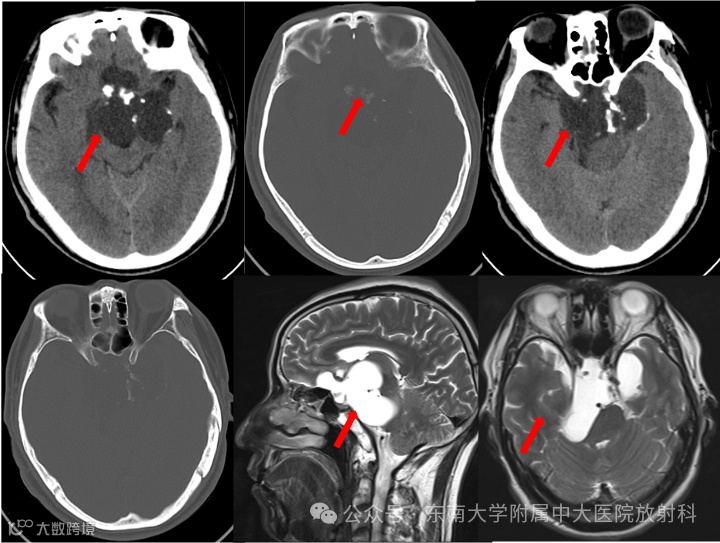

患者,男,57岁

主诉:右面部麻木伴记忆减退10月余,发现鞍区占位10月

现病史:患者 10 月余前无明显诱因出现右侧面部麻木感,伴有记忆力减退情况,至当地医院检查示鞍区占位,定期复查,未予特殊处理。双眼视物模糊,左侧较明显,无发热寒战,无言语功能障碍,无肢体感觉异常,无心慌胸闷,无腹痛腹胀。现患者为求进一步诊治至我院就诊,门诊拟“鞍区良性肿瘤”收住入院

影像学表现